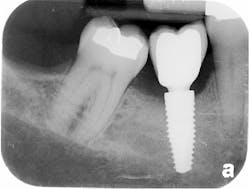

The patient was seen four months later for Stage II uncovering of her implant using a tissue punch and was sent to her restorative dentist for final impressions two weeks after that. Three months after the initial surgery, the patient returned with her final restoration in place for a soft-tissue exam and radiograph. Six months after surgery, she returned for a postdelivery radiograph, shown here. (I see every implant patient three months after seating the final restoration to check for residual cement, ensure that the restorative apparatus is fully seated, and check the soft- and hard-tissue response to the new restoration. This is an extremely important—and often overlooked visit—where problems are often noted that can cause significant damage to the bone and gingiva if early intervention is not initiated.) The bone levels were well-maintained around the implant platform, and the soft-tissue health was excellent. The patient reported a high degree of satisfaction with her new implant restoration.